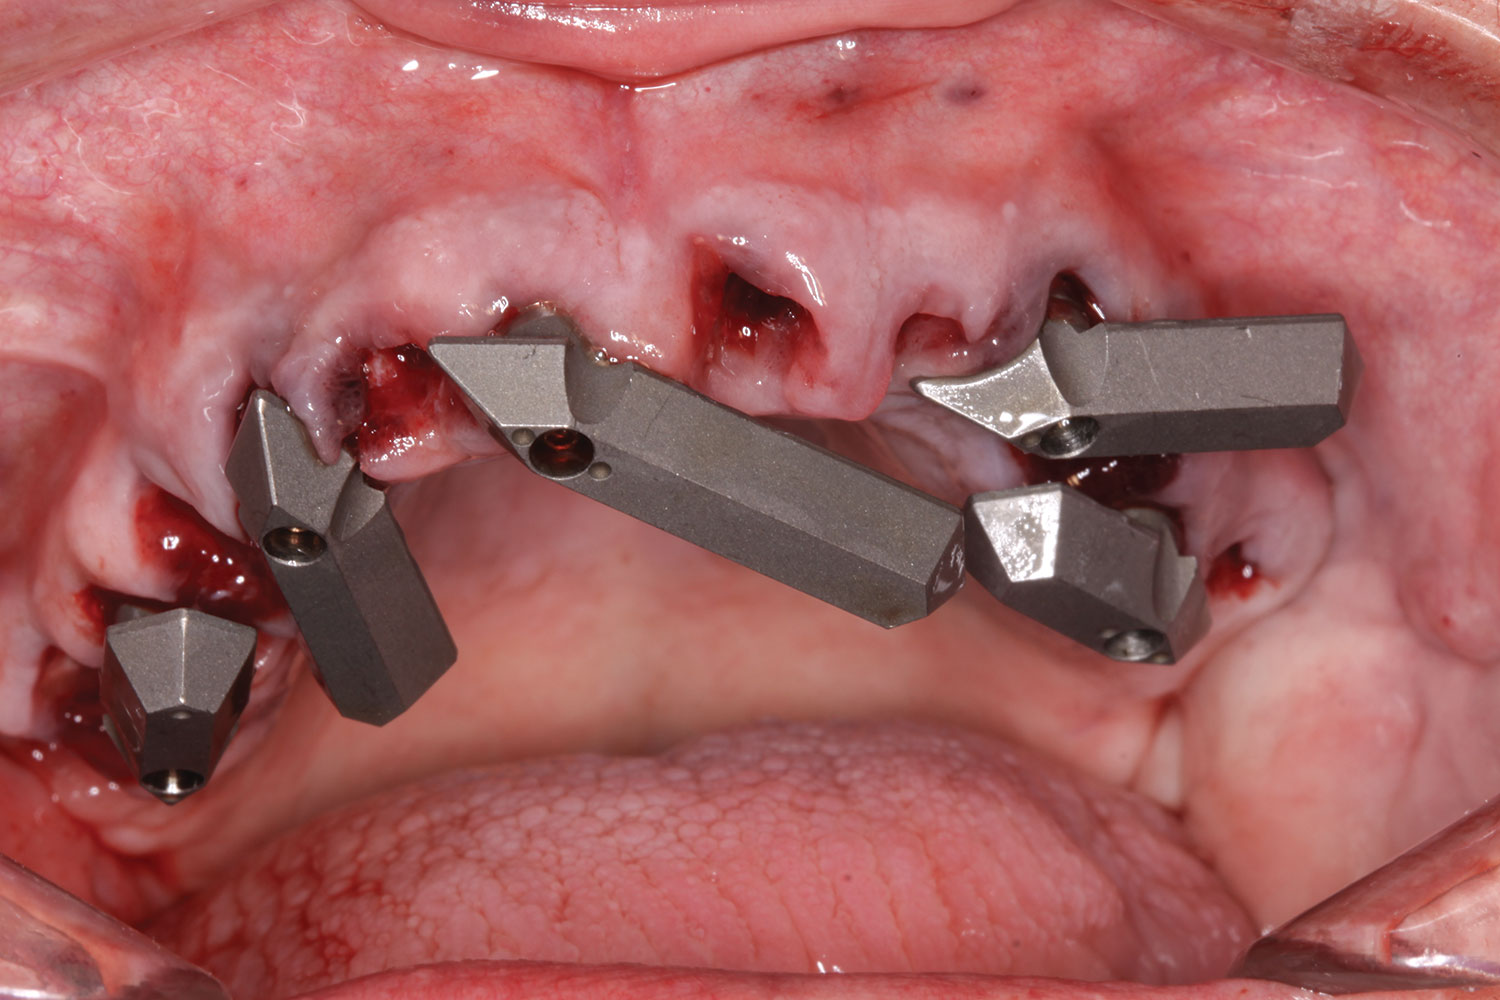

A week later the patient presented for surgery for extraction and replacement of her existing maxillary dentition with implants and a screw-retained provisional implant restoration. Teeth Nos. 2, 4, and 6 through 11, 13, and 14 were carefully extracted with attention paid to retaining site dimensions. Immediate implants were inserted into sites Nos. 4, 6, 8, 11, and 13 with high insertion torques in excess of

40 Ncm. Subsequently, multi-unit abutments were placed on all the implants and torqued to 30 Ncm, and scan gauges were placed on implant Nos. 8 and 11 (Figure 12 and Figure 13).

A maxillary intraoral scan was obtained with a digital scanner capturing the two remaining teeth in sites Nos. 5 and 12 and the scan gauges on implants Nos. 8 and 11. Subsequently, teeth Nos. 5 and 12 were extracted. Scan gauges were placed on implants Nos. 4, 6, and 13. At this time, another intraoral scan was captured of all the scan gauges on the five implants with the surrounding soft tissues (Figure 14 and Figure 15).

Fig 12. Partial extractions and placement of implants and multi-unit abutments.

Figure 12

Fig 13. Initial scan of scan gauges with residual teeth retained for reference.

Figure 13

Fig 14. All implants, multi-unit abutments, and scan gauges in place.

Figure 14

Fig 15. Completion of maxillary flapless immediate implant surgery and placement of multi-unit abutments.

Figure 15